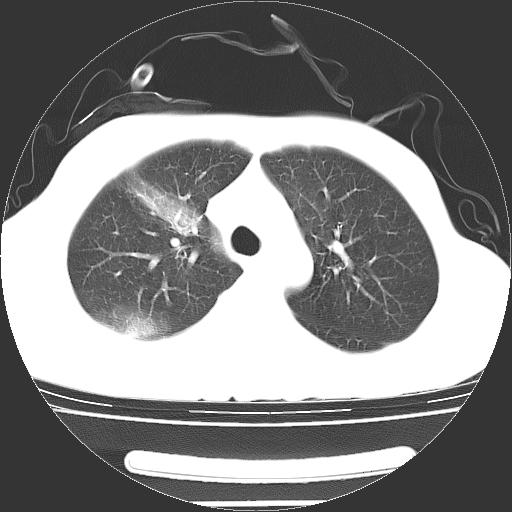

以下是引用dyqct在2008-4-29 8:43:00的发言:[br][br] 支持右侧胸腔包裹性积血。闭式引流管是不是插的太深了?

以下是引用zjzjr在2008-4-29 14:11:00的发言:[br]支持右侧胸腔包裹性积血。闭式引流管是不是插的太深了?胸腔引流,引流管快进入纵隔了.